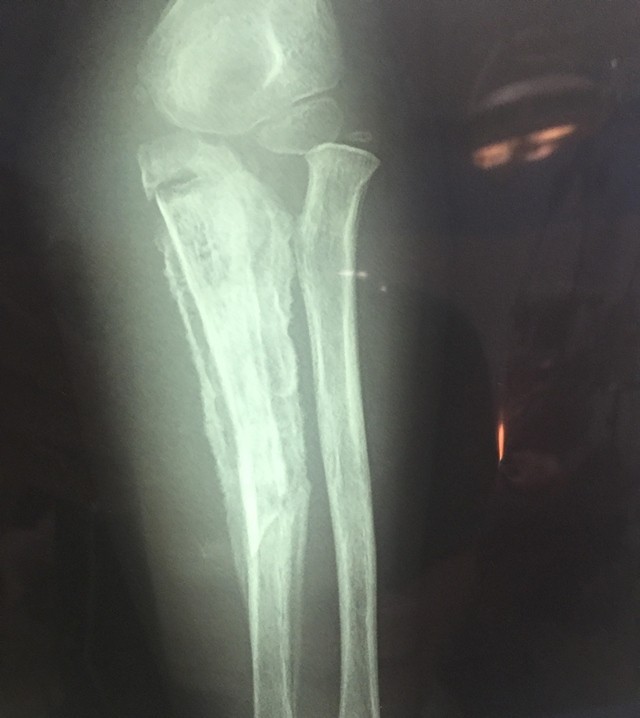

Kết quả chụp X-quang cho thấy hình ảnh viêm xương trụ,  một  đoạn xương ở vị trí 1/3 giữa trên đã hoại tử, khuỷu tay hạn chế gấp duỗi, các ngón tay co gấp, không duỗi được. Bé M. đã được chỉ định phẫu thuật ngay trong ngày.

Hình ảnh phim chụp X-quang cẳng tay bệnh nhi - Ảnh: VTV